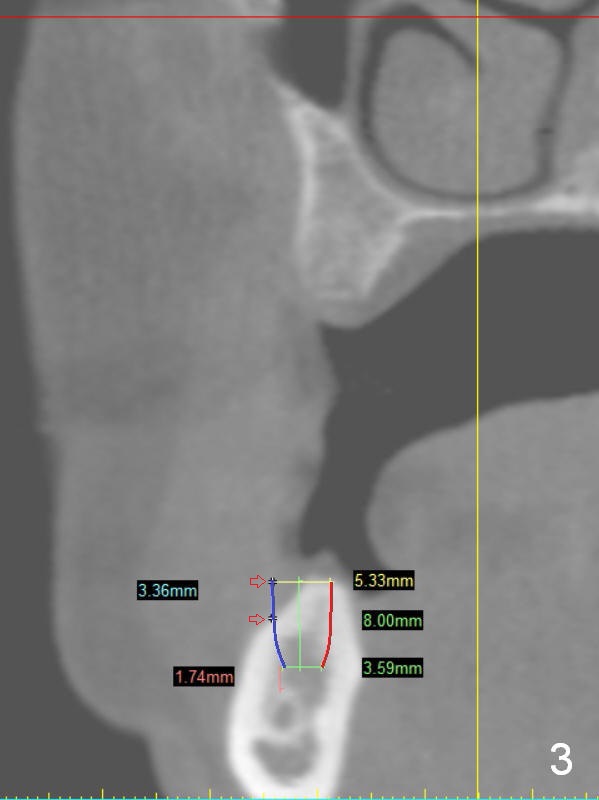

A 49-year-old lady is petit. An implant is placed at #3 and ready for restoration. The crest at #30 is narrow (Fig.1 ^). Bone density at the cortex, around the Inferior Alveolar Canal (IAC) and the medulla is D1, D2 and D3, respectively. It appears that a 10 mm bone-level implant is too close to IAC (Fig.2), whereas a 8 mm one has enough clearance (Fig.3,4). With the same diameter, there will be less thread exposure if the implant is placed a little lingually (Fig.4 (between arrows), as compared to Fig.3).

Since the patient is small and the cortex is dense, a 4.5x8.5 mm UF implant should meet masticatory force as long as #14 and 19 also receive implants. Her mouth should be small. Consider using sensor 1.舌侧骨板厚,适当磨去,让植体舌侧移动。